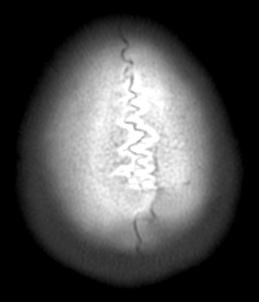

두개골 수술 또는 골절 의심되는 상황인데 엑스레이와 ct사진을 한번 봐주실 수 있나요?

2~3일 정도 기억이 없었는데 그때 머리를 다쳤는지 바로 x-ray와 ct를 찍어봤는데 한번 봐주실 수 있을까요? 진단 목적이 아닌 확인 목적입니다

빨갛게 동그라미 친 곳은 금속물질이 의심도는 부근입니다